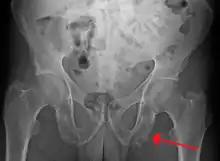

| Enthesopathy of the pelvis likely due to ankylosing spondylitis | |